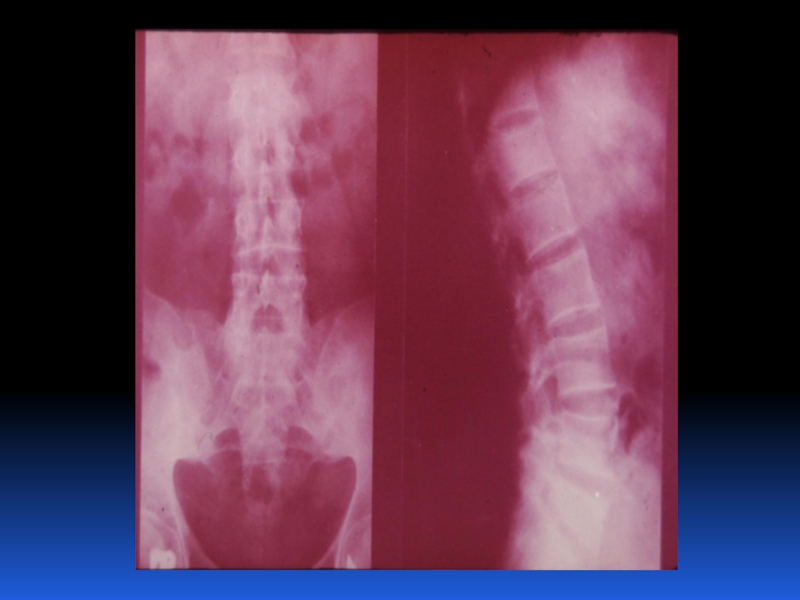

Остеопороз – это системное заболевание скелета, характеризующееся снижением костной массы и нарушением микроархитектоники костной ткани, с последующим увеличением хрупкости костей, со склонностью к патологическим переломам.

Слайд 2 Остеопороз – это системное заболевание скелета, характеризующееся снижением костной

массы и нарушением микроархитектоники костной ткани, с последующим увеличением хрупкости

костей, со склонностью к патологическим переломам.

Остеопороз – это системное заболевание скелета, характеризующееся снижением костной массы и нарушением микроархитектоники костной ткани, с